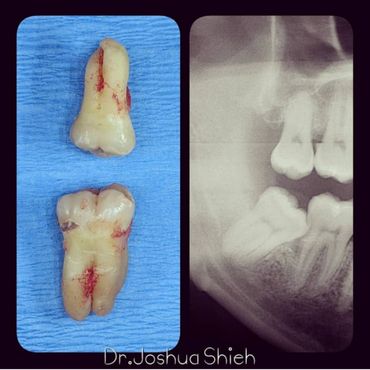

If the tooth is planned for extraction, an x-ray of the area will be taken to plan for the type of extraction.

Simple extractions are performed on erupted teeth that have regular anatomy (root and crown), and are not severely broken.

Early Wisdom Teeth Extraction

Wisdom teeth are the third set of human molars. Unfortunately, in some cases, those teeth are impacted fully or partially in bone or soft tissue and cannot erupt causing pain, discomfort and swelling. Additionally, most people have difficulty accessing these teeth during brushing or flossing causing accelerated decay and gum problems. Wisdom teeth have also been notorious for causing crowding, improper bites and pressure when they start erupting. The arrival of these late-breaking teeth can cause trouble as they are often impacted (trapped in the jawbone) because there is not enough room for them in the mouth. Our jaws are a lot smaller than those of our early human ancestors, who needed bigger jaws and more teeth for the type of food they chewed. In most people, wisdom teeth can do more harm than good and we often recommend their removal.

It can take a long time for wisdom teeth to erupt and you may not even notice the harmful effects in your mouth until you experience sudden and severe discomfort. Cramped for room, impacted wisdom teeth grow out at odd angles or remain trapped below the gums. Adjacent teeth can become prone to decay because of the unfavourable position of the wisdom teeth.